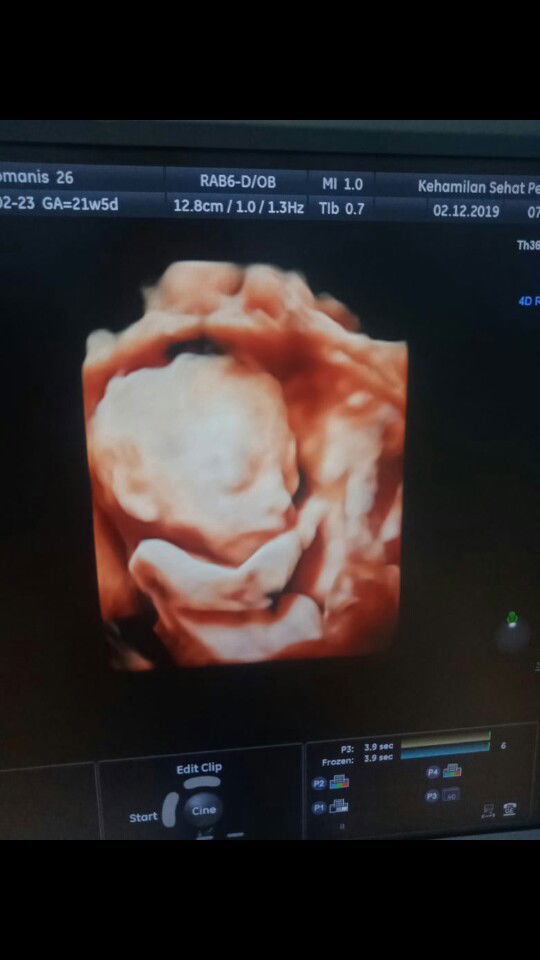

sedang mengandung